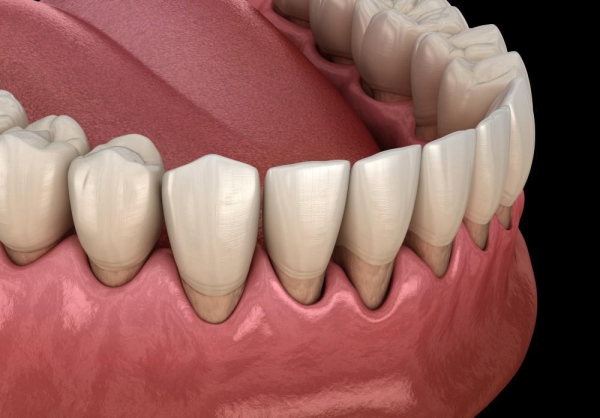

牙周病顧名思義就是「牙齒周圍」的疾病,主要發生在牙齒和牙齦的交界處,任何年齡都有可能發生,因為是慢性細菌感染所造成,因而又好發於成年人。造成牙周病的主因為口腔清潔不當,牙齒長期附著著無色黏稠薄膜中的細菌,導致牙齦出現發炎紅腫、敏感、流血甚至齒槽骨被破壞。有抽菸習慣、家族史有牙周病、糖尿病也是牙周病的高危險群。

牙周病是漸進式的,初期其實不容易被察覺,不像蛀牙可能會出現疼痛、有孔洞的情形。常見的症狀像是牙齦紅腫發炎,刷牙或使用牙線時容易流血,若放任發炎問題不管,停留在口中的細菌發酵,會導致持續性口臭問題,也會造成牙齦開始萎縮、牙縫變大,牙齒看起來變長,當齒槽骨被破壞到一定程度時,就像房子的地基被掏空,牙齒就會開始動搖甚至鬆脫。

上圖中箭頭所指處因牙齦下結石堆積,因而造成牙齦呈現紅腫狀態。

經由牙周治療去除結石後可見牙齦恢復健康,呈現粉紅色且不再紅腫,但牙齦

消腫後會造成牙齦萎縮,而萎縮程度跟齒槽骨破壞程度相關。